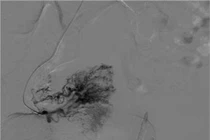

Dưới hướng dẫn của hệ thống chụp mạch xóa nền 2 bình diện DSA, các bác sĩ luồn ống thông chuyên dụng đến vị trí ổ dị dạng và tiến hành nút mạch bằng keo sinh học và coil. Kiểm tra thấy các nhánh động mạch tử cung hai bên cấp máu cho ổ thông động tĩnh mạch đã được nút tắc hoàn toàn và triệt để.

Hình ảnh ổ thông động tĩnh mạch tử cung với nguồn cấp máu phức tạp được kíp can thiệp nút mạch loại bỏ hoàn toàn - Ảnh BVCC